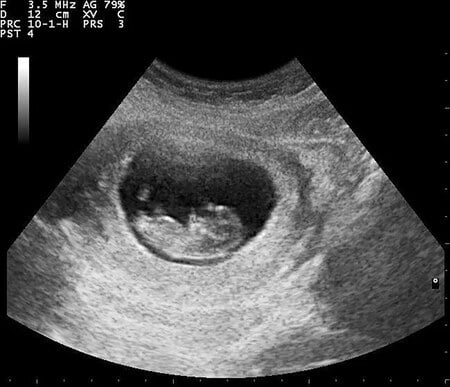

備孕時的孕前檢查、自我調理,還有要相信只要健康生活一定很快就有好消息。期間凱妞加入備孕相關的社團,其實多數人的方法就是補充營養,不夠的就吃營養食品來補充,再來就是增加運動量讓自己變健康,終於凱妞在結婚後,歷經四年的時光,終於懷上小楊桃!